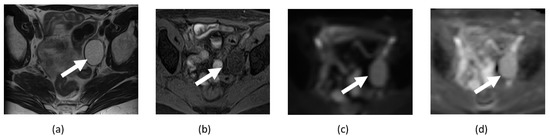

4.3. Ovarian Cancer

- Thomassin-Naggara, I.; Daraï, E.; Cuenod, C.A.; Fournier, L.; Toussaint, I.; Marsault, C.; Bazot, M. Contribution of diffusion-weighted MR imaging for predicting benignity of complex adnexal masses. Eur. Radiol. 2009, 19, 1544–1552. [Google Scholar] [CrossRef]

- Sadowski, E.A.; Thomassin-Naggara, I.; Rockall, A.; Maturen, K.E.; Forstner, R.; Jha, P.; Nougaret, S.; Siegelman, E.S.; Reinhold, C. O-RADS MRI Risk Stratification System: Guide for Assessing Adnexal Lesions from the ACR O-RADS Committee. Radiology 2022, 303, 35–47. [Google Scholar] [CrossRef]

- Türkoğlu, S.; Kayan, M. Differentiation between benign and malignant ovarian masses using multiparametric MRI. Diagn. Interv. Imaging 2020, 101, 147–155. [Google Scholar] [CrossRef] [PubMed]

- Derlatka, P.; Grabowska-Derlatka, L.; Halaburda-Rola, M.; Szeszkowski, W.; Czajkowski, K. The Value of Magnetic Resonance Diffusion-Weighted Imaging and Dynamic Contrast Enhancement in the Diagnosis and Prognosis of Treatment Response in Patients with Epithelial Serous Ovarian Cancer. Cancers 2022, 14, 2464. [Google Scholar] [CrossRef] [PubMed]